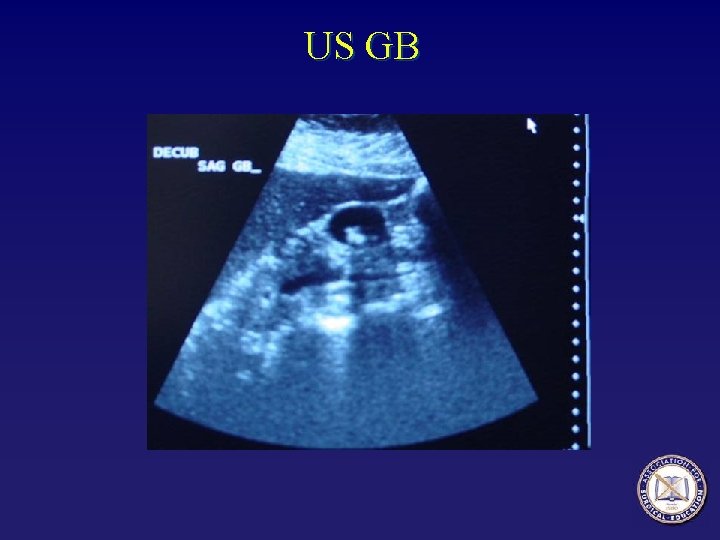

US GB

Discussion of Studies • Ultrasound of right upper quadrant is indicated to evaluate gallbladder and bile duct for stones. • CT scan should be done after initial stabilization. IV contrast is useful to assess pancreatic viability. Use of IV contrast on presentation is debated.